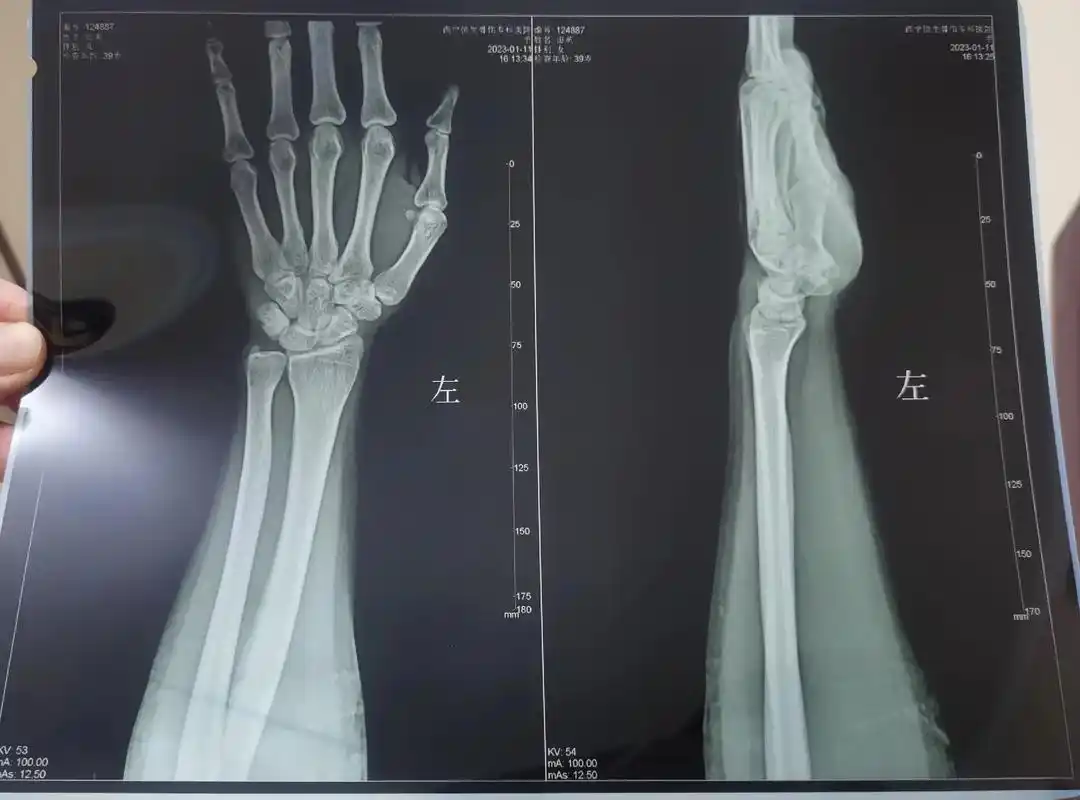

手腕背伸肌腱炎不能用力不能拧毛巾疼得一只碗都端不动